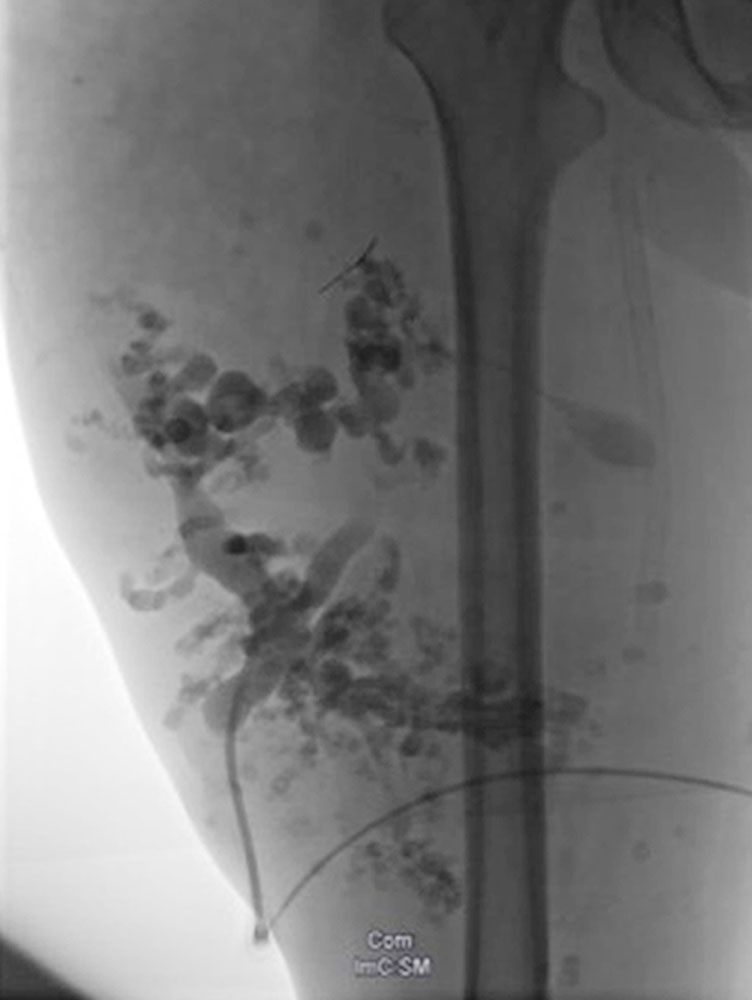

The accompanying vascular malformations do not always occur but, in addition to the increased likelihood of tumor occurrence, are often determinant of the disease course or symptomatology. Relatively characteristic are the often progressive, circumscribed soft tissue changes known as PHOST (PTEN Hamartoma Of Soft Tissue), which histologically present as mixed vascular and soft tissue malformations (capillary, venous and lymphatic malformations) embedded in atypically increased hyperplastic adipose tissue. Concomitant arteriovenous fast-flow malformations are characterized by more spherical, intranidal, or venous “flow-related” aneurysms and frequently recur after treatment.